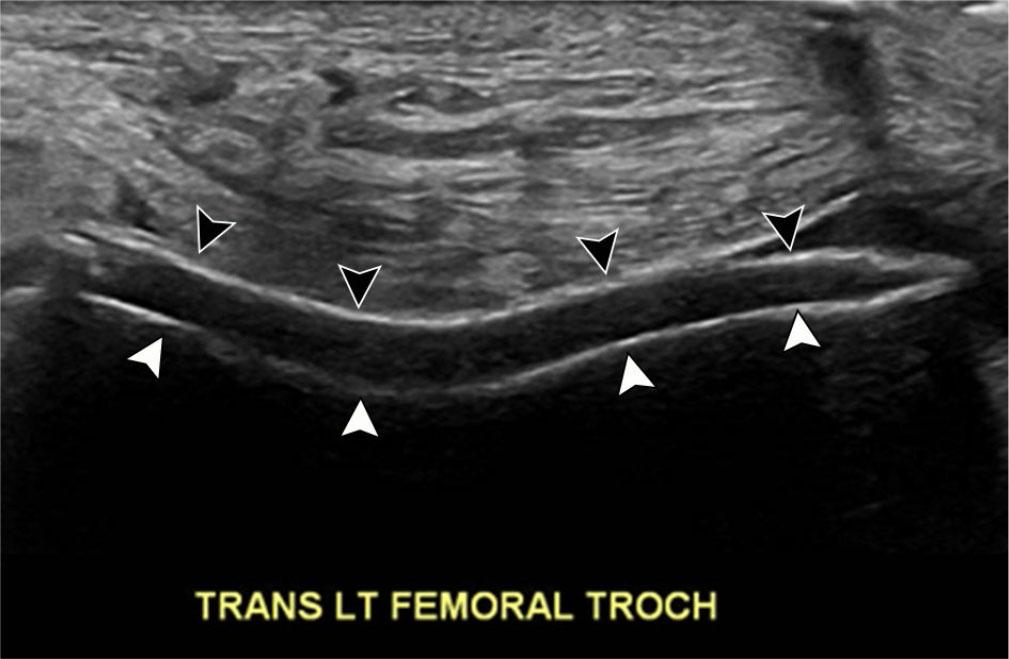

With their deep position, visualizing the entirety of the cruciate ligaments at US is challenging(23). To evaluate the cruciate ligaments at US, the patient is placed prone, with the knee flexed at approximately 20 degrees(24). The tibial insertion of the anterior cruciate ligament (ACL) may be better visualized with the patient in the supine position, with maximal passive flexion of the knee (Fig. 5 A(25). The probe is oriented longitudinally along the patellar tendon with rotation of the cranial aspect of the probe towards the medial aspect of the lateral femoral condyle(26). Patient pain and swelling potentially limit visibility with this approach.

Fig. 5.

53-year-old female with knee pain, unable to undergo MRI. A. Longitudinal grayscale US image slightly oblique to the patellar tendon with knee flexion demonstrates no tear at the tibial insertion of the anterior cruciate ligament (ACL) (arrowheads). T – tibia, F – femur. B. Longitudinal grayscale US image at the central posterior tibial plateau with knee flexion demonstrates no tear at the tibial insertion of the posterior cruciate ligament (PCL) (arrowheads). The femoral origin of either ligament is not visible

Even with optimal positioning, the ACL remains difficult to directly visualize, and diagnosis of tear relies on indirect signs, such as abnormal hypoechogenicity or a discrete fluid collection in the expected location of the ACL(23). The tibial insertion of the posterior cruciate ligament (PCL) is directly visible when imaging with the posterior approach (Fig. 5 B(2). Heterogeneity and/or thickening of the PCL >10 mm with ill-defined margins at US reflects injury, but does not readily identify proximal tears (Fig. 6)(27).